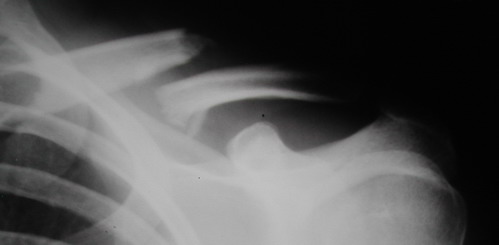

Во время стажировки в Австрии не мог не поинтересоавться, как австрийские хирурги лечат переломы ключицы. Оказалось, при переломах без смещения или с небольшим смещением накладывают восьмиобразную повязку, в остальных случаях выполняют остеосинтез пластинами.

Хотя с точки зрения кожных рубцов на видном месте, рамка Чижина и аппарат имеют явное преимущество. Но в ущерб "качеству сна"...